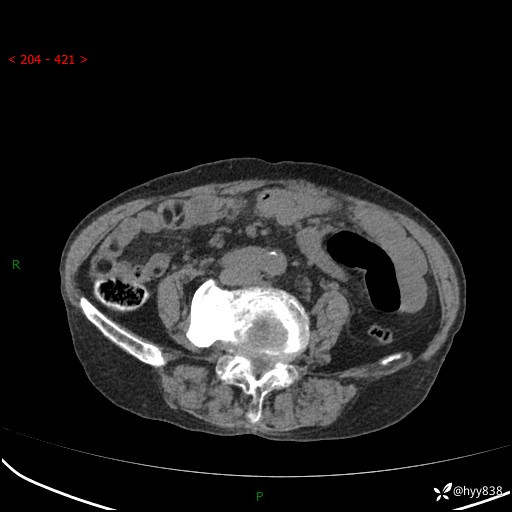

全腹部CT平扫